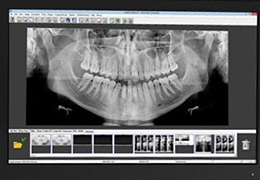

ANYTHINK 经导管主动脉瓣膜置换术分析系统